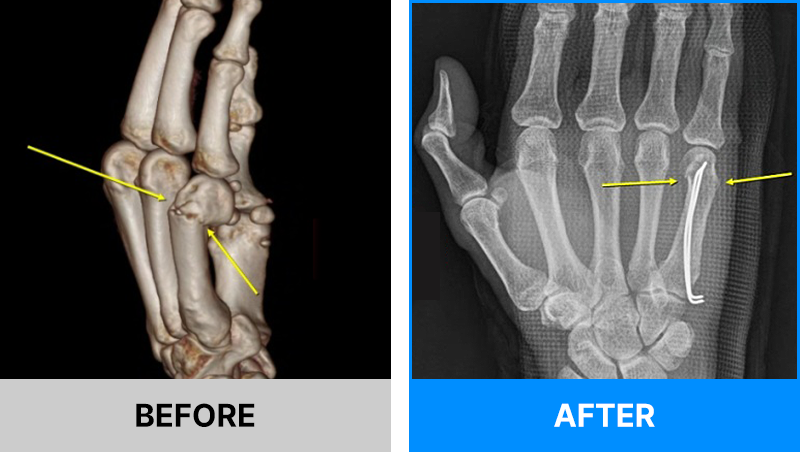

왜 당일 입퇴원 수술일까요?

오래 입원할 필요가 없기 때문입니다.

서울거탑정형외과에서는 전신마취, 척추마취가 아닌

국소부분마취(신경차단) 및 수면 마취를 통해 수술을 시행합니다.

수술 가능 여부 확인은 대표원장과의 진료가 필요합니다.